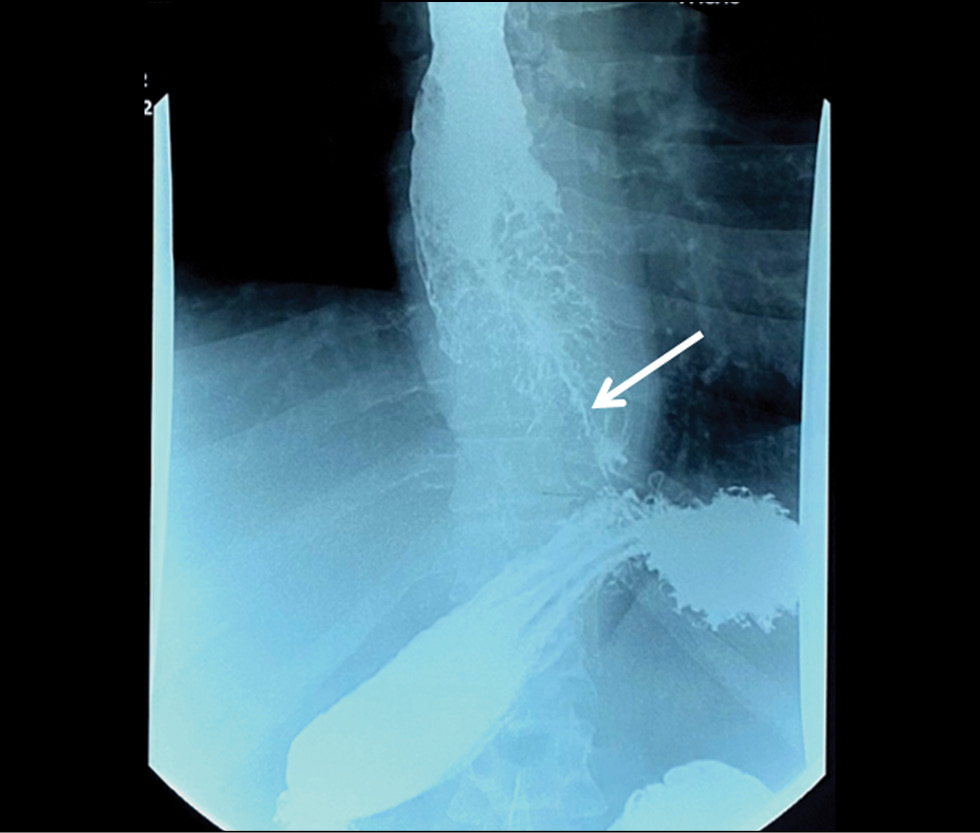

В статье описано клиническое наблюдение пациента с прогрессирующей дисфагией, вызванной опухолью пищевода, распространяющейся на субкардиальный отдел желудка, которую не удавалось патоморфологически верифицировать в течение одного года. Данные эзофагогастродуоденоскопии, выполненной в медицинской организации по месту жительства, компьютерной томографии и рентгеноскопии пищевода с двойным контрастированием не оставляли сомнений в злокачественности новообразования, однако результаты многочисленных гистологических исследований свидетельствовали в пользу аденомы пилорических желёз, аденомы из париетальных, либо онкоцитарных клеток с фокусами дисплазии эпителия высокой степени. Эндоскопическое исследование с таргетированной биопсией в условиях специализированного учреждения позволило доказать злокачественность опухолевого процесса.